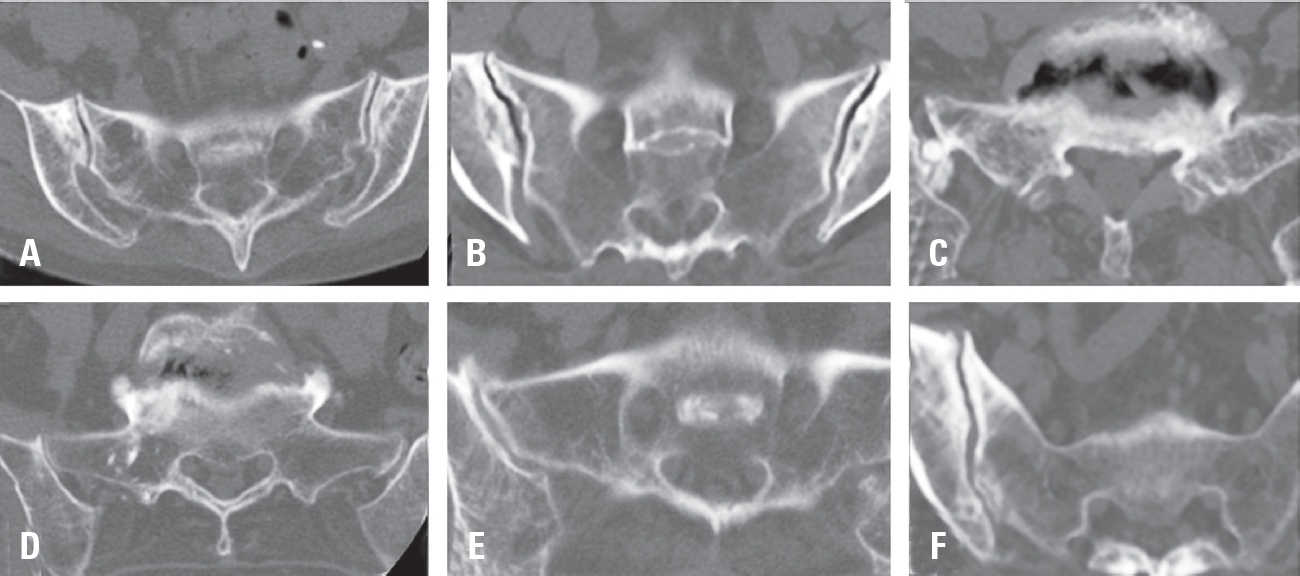

Sacroiliac Joint Degeneration Following Lumbar Fusion: What are the Risk Factors?

Woo-Seok Jung, Min Ho Lee, Ji-won Kwon J Adv Spine Surg 2025;15(2):94-103. -